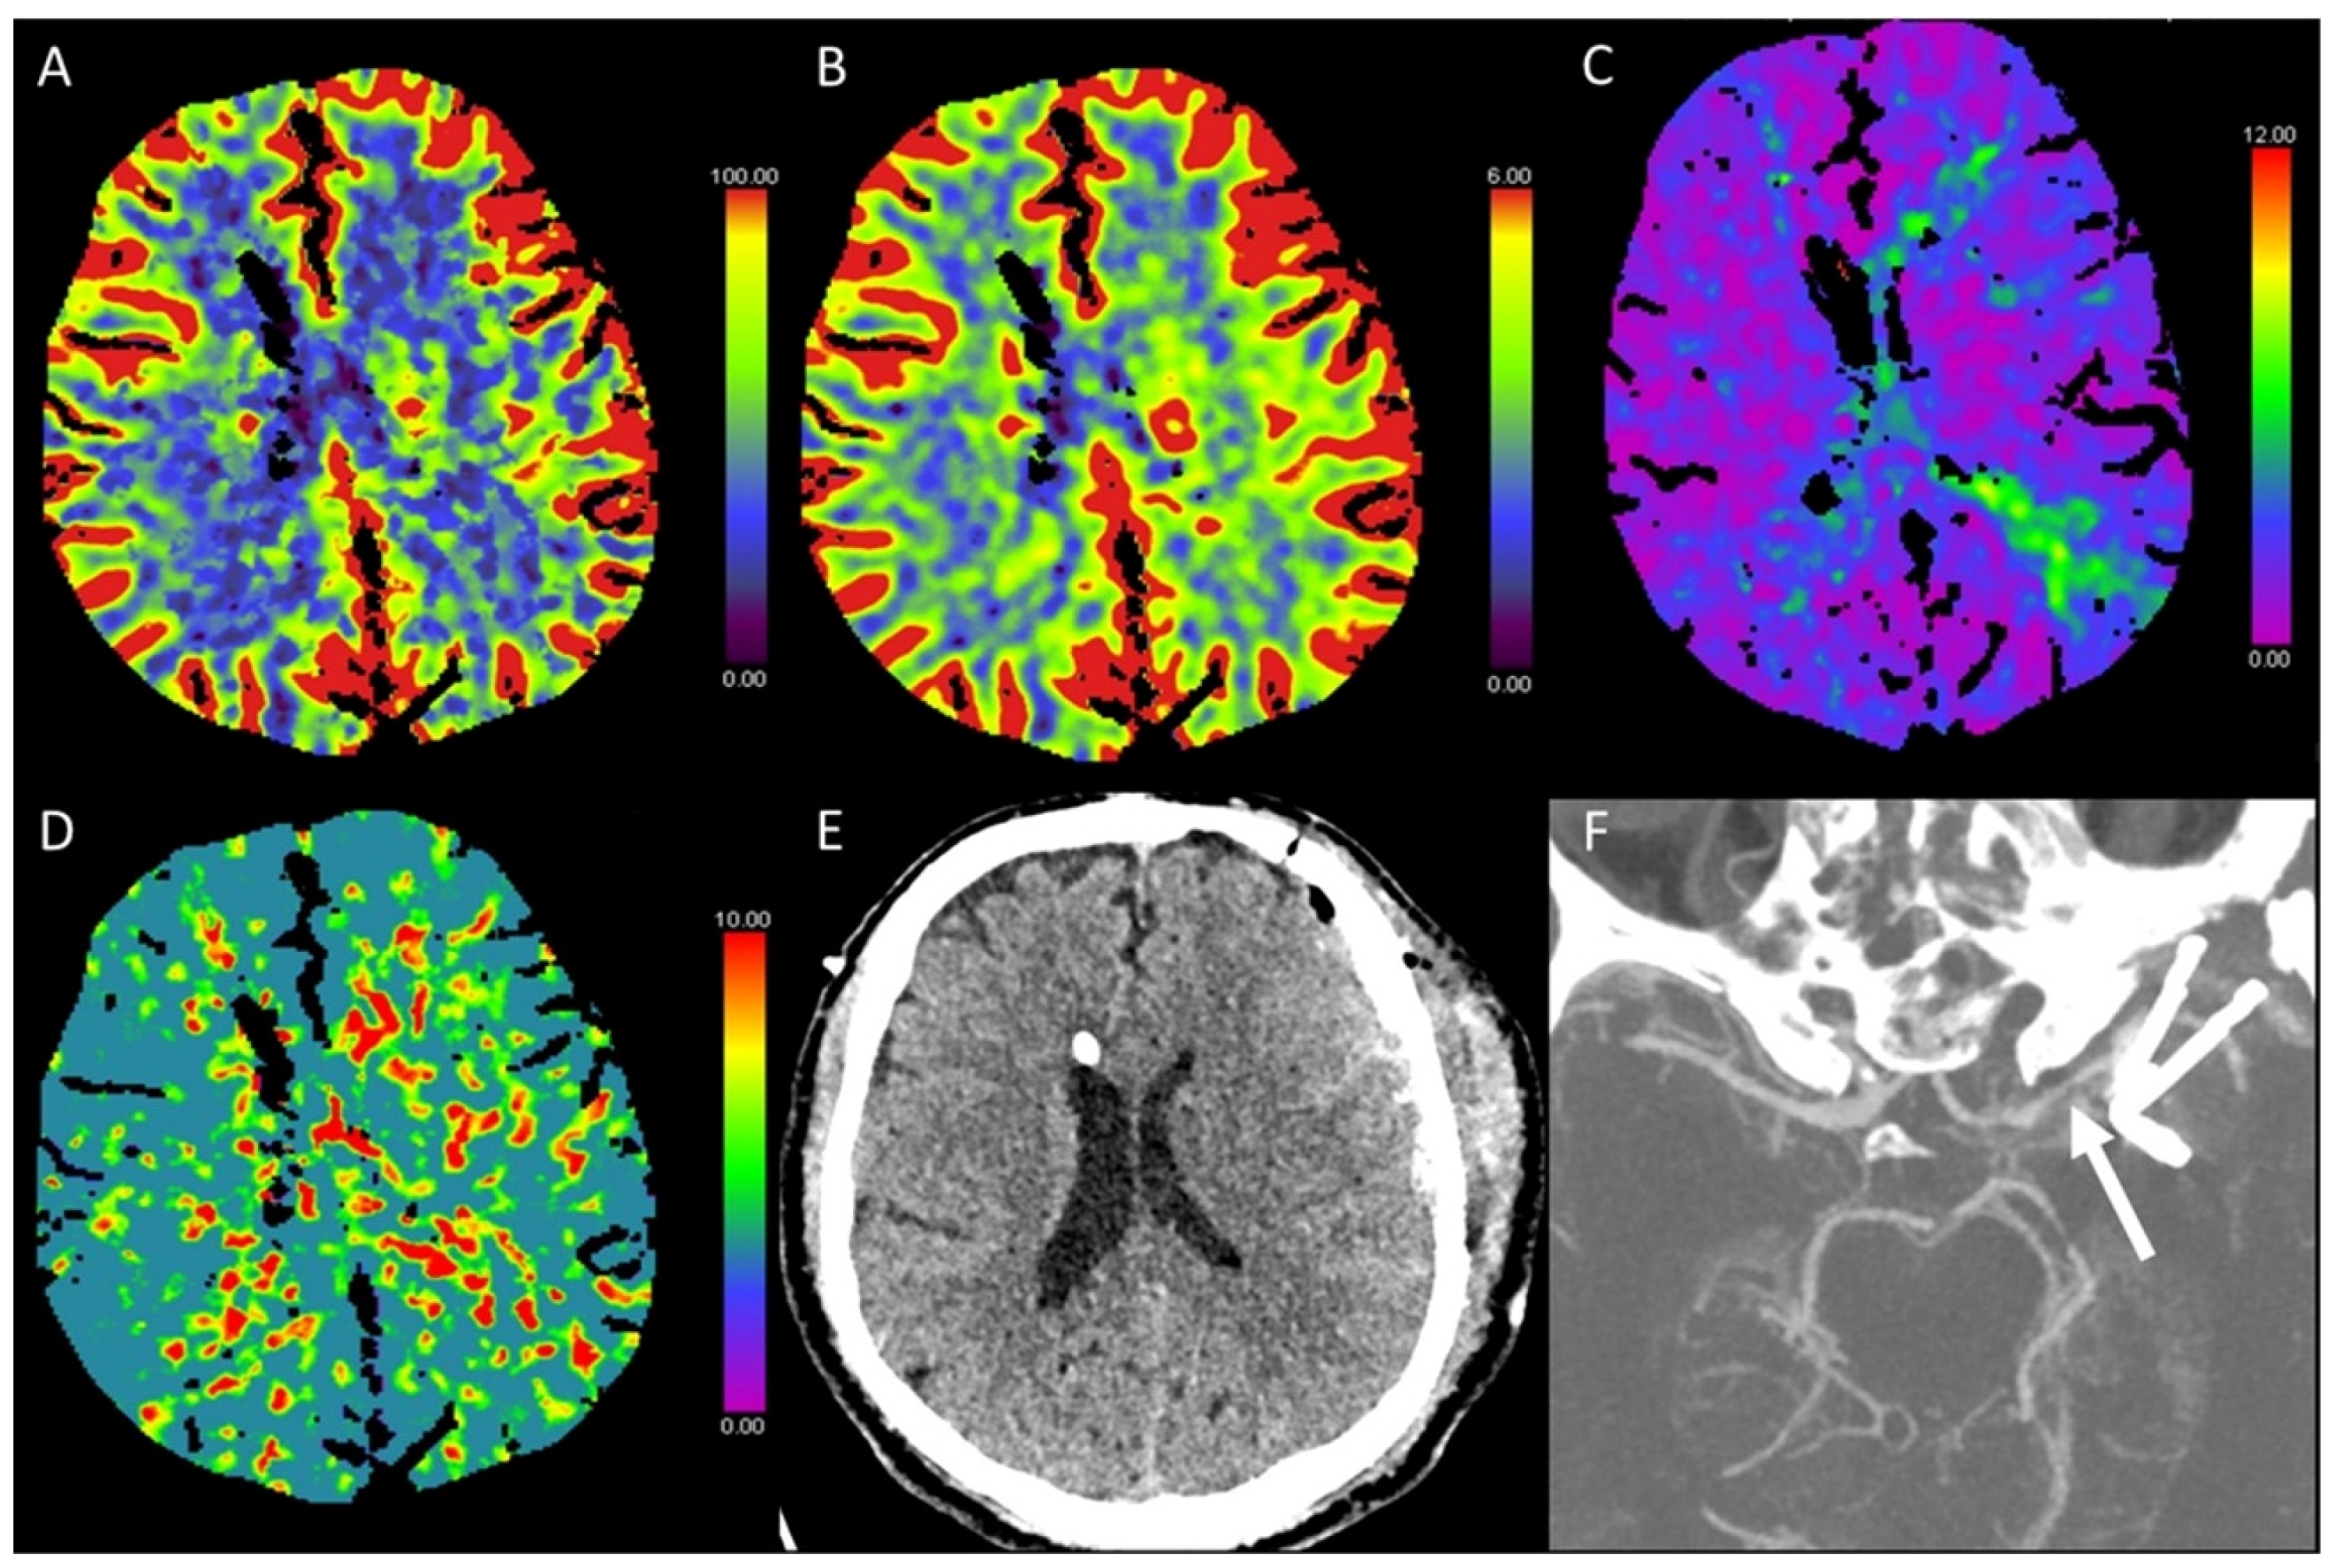

3.6. Vasospasm

- Kassell, N.F.; Sasaki, T.; Colohan, A.R.; Nazar, G. Cerebral vasospasm following aneurysmal subarachnoid hemorrhage. Stroke 1985, 16, 562–572. [Google Scholar] [CrossRef] [PubMed]

- Othman, A.E.; Afat, S.; Nikoubashman, O.; Muller, M.; Schubert, G.A.; Bier, G.; Brockmann, M.A.; Wiesmann, M.; Brockmann, C. Volume perfusion CT imaging of cerebral vasospasm: Diagnostic performance of different perfusion maps. Neuroradiology 2016, 58, 787–792. [Google Scholar] [CrossRef] [PubMed]

- Cremers, C.H.P.; van der Schaaf, I.C.; Wensink, E.; Greving, J.P.; Rinkel, G.J.E.; Velthuis, B.K.; Vergouwen, M.D.I. CT perfusion and delayed cerebral ischemia in aneurysmal subarachnoid hemorrhage: A systematic review and meta-analysis. J. Cereb. Blood Flow Metab. 2014, 34, 200–207. [Google Scholar] [CrossRef]

- Aralasmak, A.; Akyuz, M.; Ozkaynak, C.; Sindel, T.; Tuncer, R. CT angiography and perfusion imaging in patients with subarachnoid hemorrhage: Correlation of vasospasm to perfusion abnormality. Neuroradiology 2009, 51, 85–93. [Google Scholar] [CrossRef]